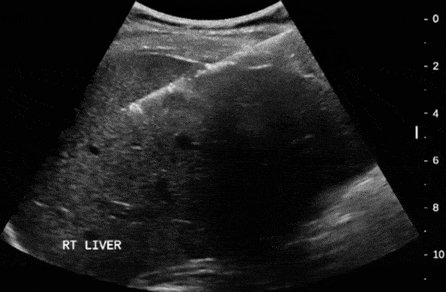

Diğer biyopsi işlemleri ise ultrason eşliğinde yapılabilir. Diğer tru-cut biyopsi işlemlerinde olduğu gibi steril koşullar altında kitle ultrason ile görülerek yapılır. Bu yapılan kalın iğne biyopsilerinin tanısal değerleri çok yüksektir.